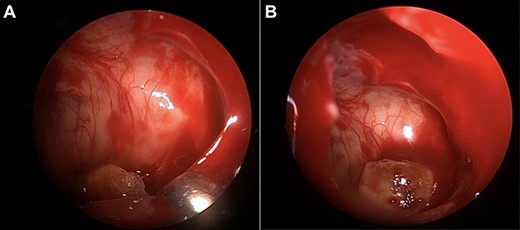

A 14-year-old female patient with no significant past medical history presented to our department 11 days following third molar extraction during which tooth number one was displaced into the right maxillary sinus cavity. A complete history and physical was performed. The patient was asymptomatic with postoperative changes along her gingiva, but the remainder of her exam was normal. There was no sinus tenderness reported on palpation or signs of sinusitis on endoscopy. A computed tomography (CT) scan of the sinuses without contrast was performed, which revealed the displaced molar within the posterior inferior maxillary sinus and a posterior maxillary wall defect (arrow, Fig. 1A and B).

(A, B) CT sinus images of a displaced third molar (arrow) into the posterior aspect of the maxillary right sinus.